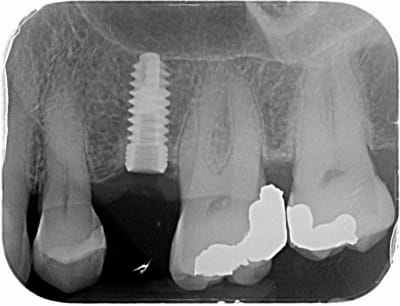

Bonjour,

Sauriez-vous de quelle marque d'implant il s'agit ?

La connexion est un hexagone interne.

Merci d'avance.